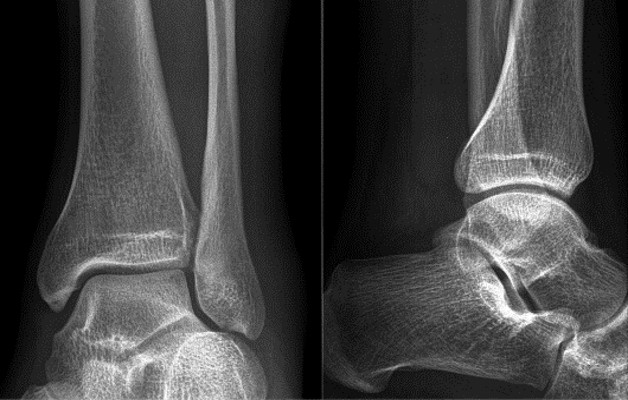

Остеофиты оказывают давление на окружающие ткани, вызывая воспаление и отеки. Для подтверждения диагноза врач назначает лабораторные и рентгенологические исследования. При возникающих вопросах проводят магнитно-резонансную томографию, которая позволяет увидеть не только кости, но и состояние мягких тканей и кровеносных сосудов.

- 1 степень. Хрящевая ткань только начинает претерпевать изменения. Сустав на рентгеновском снимке выглядит здоровым, несколько сужена суставная щель. Пациент не испытывает боль и может не догадываться о развитии болезни.

- 2 степень. Начинается давление и трение костей. По краям суставных площадок разрастаются остеофиты, суставная щель значительно сужена. Человека начинают беспокоить боли, которые усиливаются при ходьбе.

- 3 степень. На рентгене видна деформация костей, массивные остеофиты, практическое полное закрытие суставной щели, иногда наблюдаются вывихи и подвывихи. Больной чувствует постоянную боль даже в состоянии покоя. Может развиться вальгусная или варусная деформация конечности, что еще больше затрудняет ходьбу.